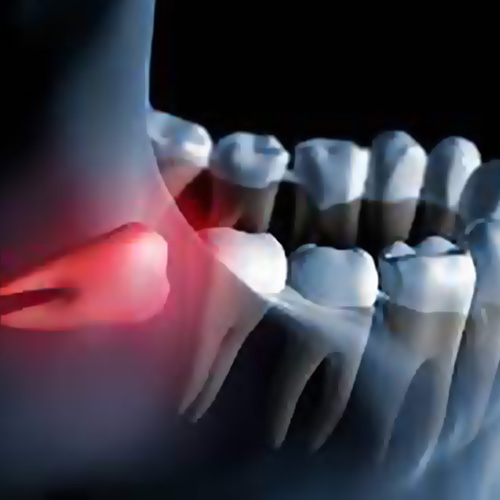

Swelling or Redness Around Gums

Inflamed or swollen gum tissue at the back of your mouth may indicate infection or impaction. A Dental abscess (which is a swelling inside or outside your mouth) is an emergency matter. You should call us immediately.

Wisdom teeth (third molars) can sometimes lead to serious complications when left untreated. Due to their position, they may damage adjacent second molars—causing erosion, cavities, or even the need for extraction if the damage becomes irreversible. In some cases, wisdom teeth also contribute to crowding, which can affect the alignment of all your teeth and lead to gum disease, bone loss, or further tooth damage.